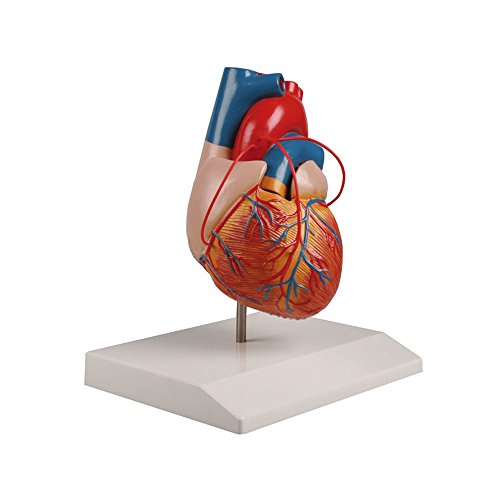

Фотографии и 3D-модели анатомии сердца человека